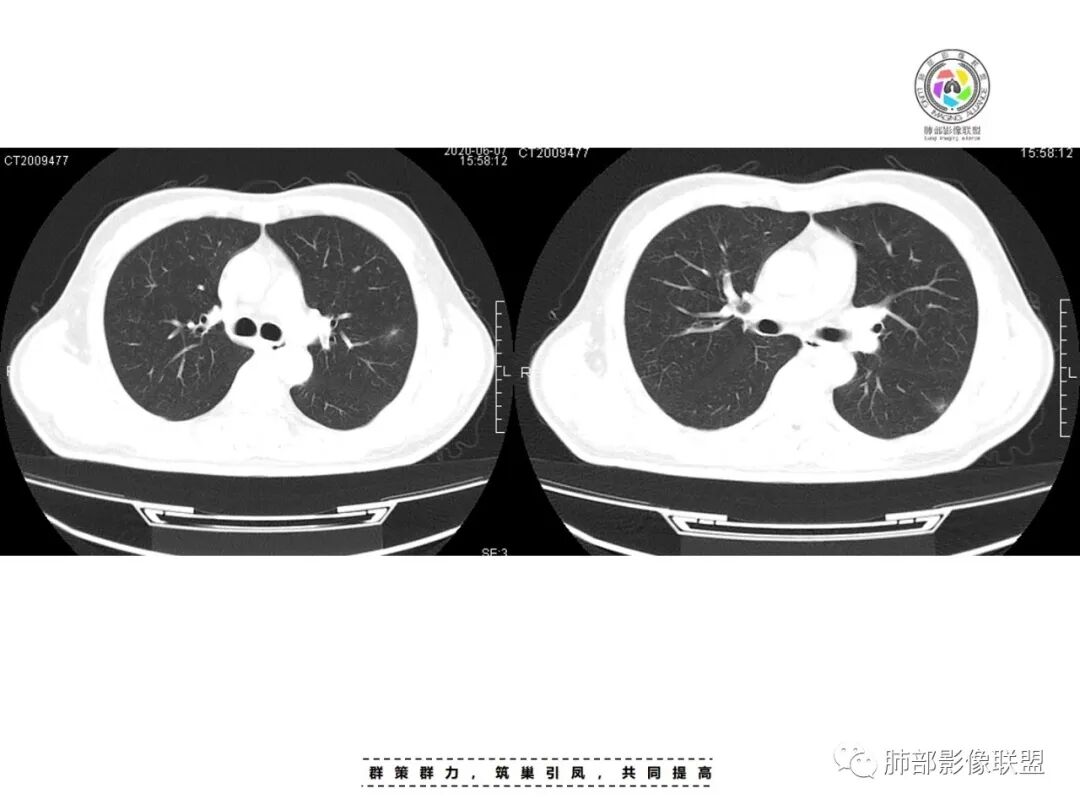

李:双肺多发结节,部分空洞,胸膜下为主,考虑血源性,治疗后好转,如果抗炎好转,考虑化脓菌栓,肺克或金葡,如激素治疗后考虑gpa亚东:双肺多发结节,部分见空洞,与血管关系紧密,考虑感染性病变,短期内变化快,糖尿病史,金葡,肺克?王秀仙:糖尿病基础上伴发的多发结节,部分空洞,四大金刚金毛结克,首选肺克琦遇:糖尿病四大金刚里按病史只有金葡和肺克符合,病灶特点,胸膜下为主,病灶偏少,有不干净空洞,肝功无异常,金葡可能性大!大雄:但是没有发热 小强:糖尿病史,胸膜下,6天空洞增大,金葡可能,肺克一般进展后有融合大片改变,这个没有,但是金葡临床症状更重,这个也看不出来崔少钢:中年男性,血糖控制不良,感染指标高。影像:双肺多发的结节、空洞,分布比较随机,考虑肺克。病变变化不够快,囊张力不够高,感觉不像金葡。大雄:血流感染的金葡 与肺克影像上有重叠,不一定好区分肺克炎性指标(PCT)可以高的更明显金葡血流感染一般有可追寻的来源,比如皮损,软组织脓肿,骨髓炎,心内膜炎等肺克一般是来源肠道,经门脉系统入肝,形成肉眼可见的肝脓肿或者不可见的隐匿性微脓肿,再经肝静脉回流→下腔静脉→右心→肺动脉→肺内播散张小兵:糖尿病基础,胸膜下多发结节伴空洞形成,这么大的空洞结节无播散,排除结核。肉芽肿性多血管炎,一般累及支气管,引起支气管狭窄,也可排除,倾向肺克,鉴别金葡。流心明智:男性,51岁,以咳嗽、咳痰、气喘3天。既往糖尿病10年。血常规wBC及中性比、CRP、PCT均升高。CT示:双肺多发结节、小斑片影,胸膜下多,大部分实性、部分伴空洞,大部分类圆形、部分呈楔形,部分病灶可见滋养血管征,治疗后逐渐吸收。考虑:感染性病变,SPE,金葡>肺克,鉴别隐球、TB等。

一、双肺多发结节或小片影,随机分布,而未见支气管壁增厚及支气管远端如树芽征等改变,提示病灶来源于血道;且肺内结节边缘模糊,常可排除转移(一般转移瘤边缘多较光整,患者常有恶性肿瘤病史,且呼吸道症状不明显或出现较迟);

影像表现:双侧结节,常伴空洞形成,最多见于肺外周和肺下野,结节的边界清晰或模糊;可伴有斑片状实变区;多表现为基底贴近胸膜的楔形实变影,其内密度均匀或不均匀,可形成空洞。